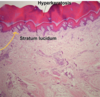

What are the layers of the epidermis from superficial to deep? What layer isn’t always present?

Stratum corneum

Stratum lucidum only present in acral skni

Stratum granulosum

Stratum spinosum

Stratum basale

Describe the structure and function of the stratum corneum?

Aka keratin layer; comprised of anucleate corneotyes.

Serves as the primary barrier of the epidermis.

Thicker at acral sites, nonexistent at mucosal sites.

Desribe the structure and function of the stratum lucidum?

Aka clear layer; only seen in acral skin.

Thin eosinophilic (or clear) band beneath stratum corneum that’s 3-5 cell layers thick.

May function to reduce friction.

What is acral skin? What are characteristics?

Thick, compact stratum corneum with prominent rate ridge pattern (arrow in picture).

Stratum lucidum present.